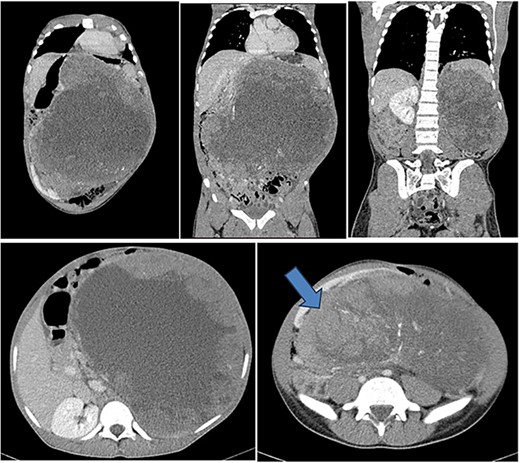

His lab results showed a leukocyte count of 7.5 × 109/l, hemoglobin of 12.8 g/dl, normal platelet count of 299 × 109/l, serum urea of 3.67 mmol/l and creatinine of 67 mmol/l. Liver enzymes were within normal range. Urinalysis revealed mild proteinuria with severe hematuria. He underwent an abdominal-pelvic CT-scan that revealed a huge left renal tumor arising from the posterior cortex of the left kidney measuring 24 cm (AP) × 28.4 cm (T) × 31 cm (CC). The left kidney is displaced to the right lower quadrant. The mass crossed the midline with displacement of the aorta and pancreas to the left side. The small bowels were displaced inferiorly into the pelvis. There was no evidence of renal artery or vein thrombosis and no obvious lymph node enlargement seen (Fig. 1).

Contrasted coronal and axial CT of the abdomen and pelvis shows a huge heterogenous solid mass with central calcifications arising from the posterior cortex of the left kidney measuring 24 cm (AP) × 28.4 cm (T) × 31 cm (CC) in size. The left kidney is displaced to the right lower quadrant (blue arrow). The mass crosses the midline with displacement of the aorta and pancreas to the right side of the abdomen. The small bowels are displaced inferiorly into the pelvis. Features are suggestive of left renal tumor.